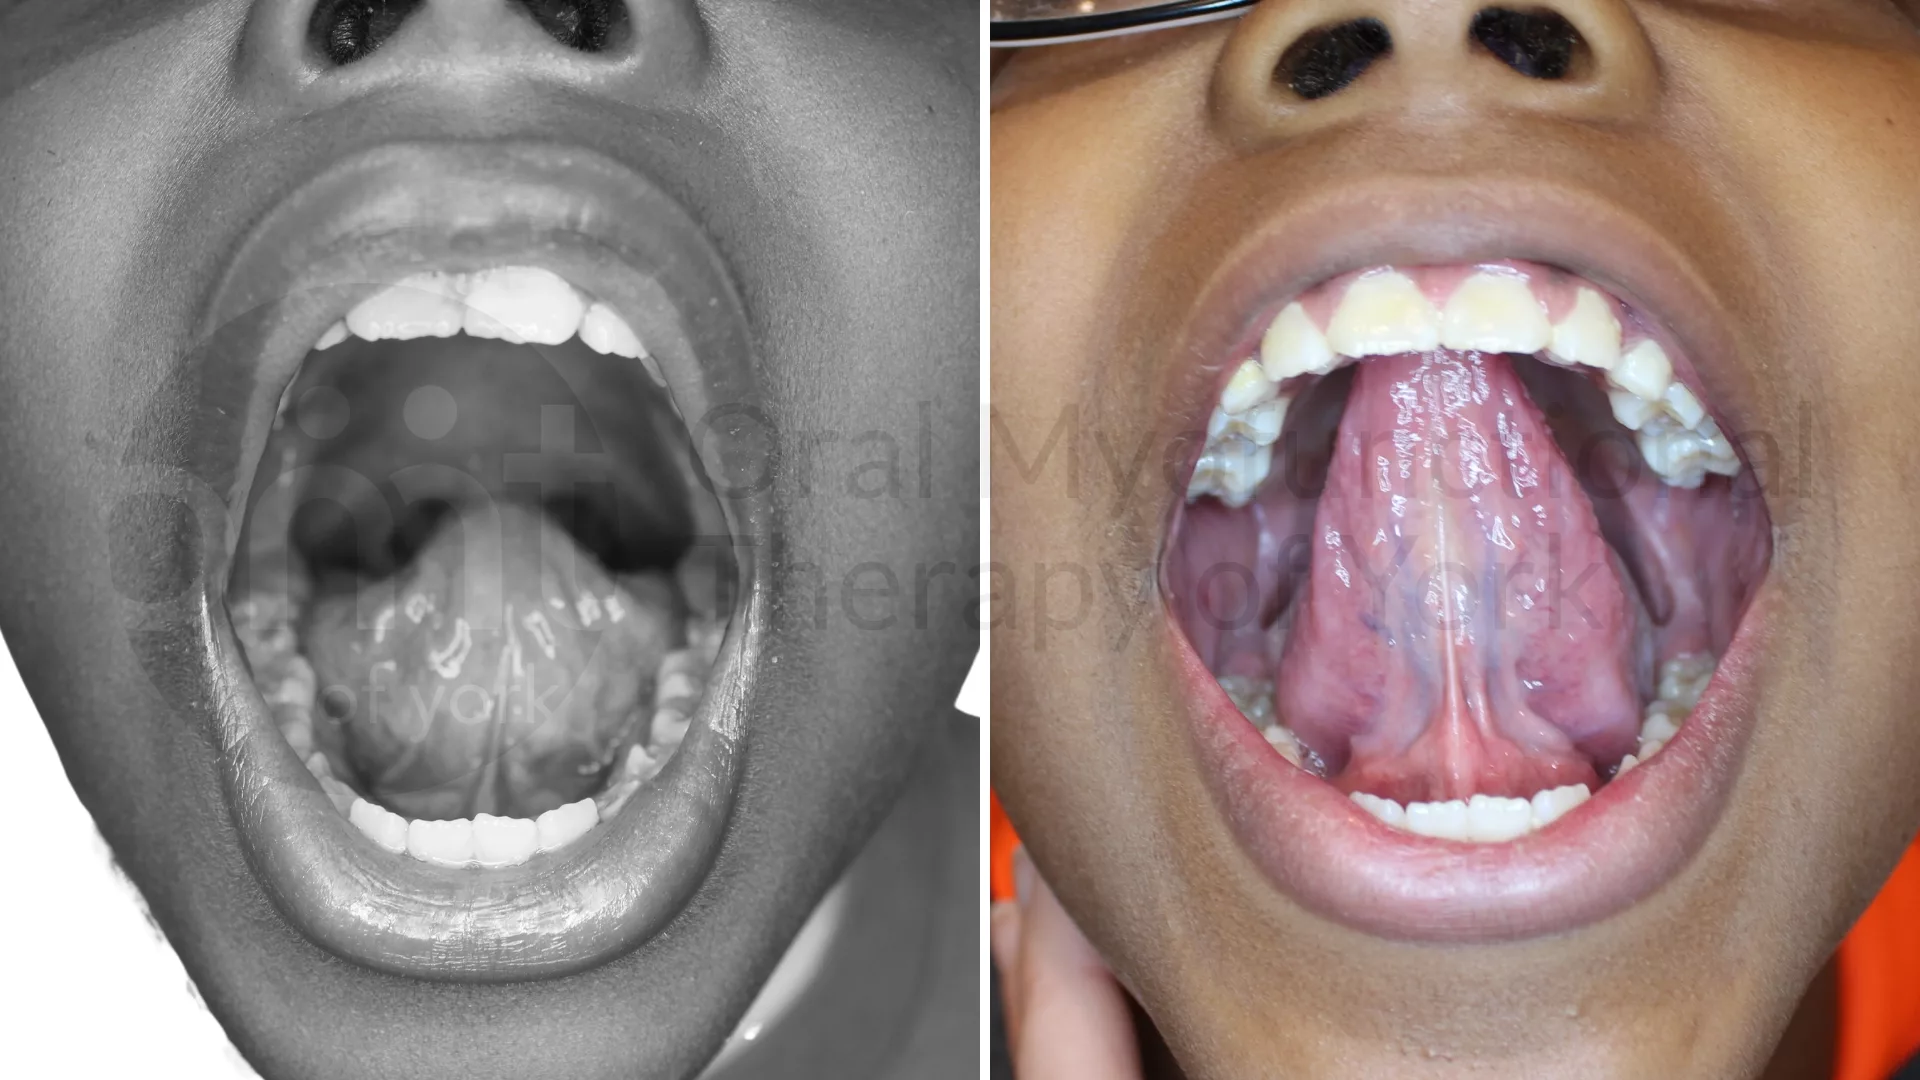

Better range of motion of the tongue from a frenectomy and therapy can lead to better growth patterns, better chewing/swallowing patterns and better overall health

This severe tongue tie was contributing to poor oral rest posture, forward head posture and poor chewing/swallowing patterns. The patient had dramatic improvements after therapy and a frenectomy.

Tongue restrictions that are often deemed “normal” by multiple medical practitioners can have a significant impact on growth and overall health. A full functional assessment is the correct way to determine if a tongue tie is present.